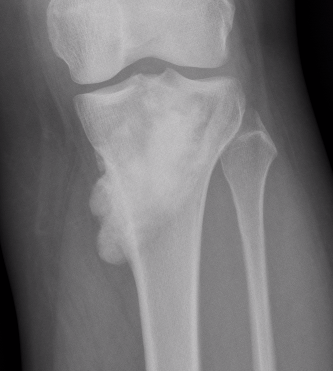

Parosteal Osteosarcoma proximal tibia